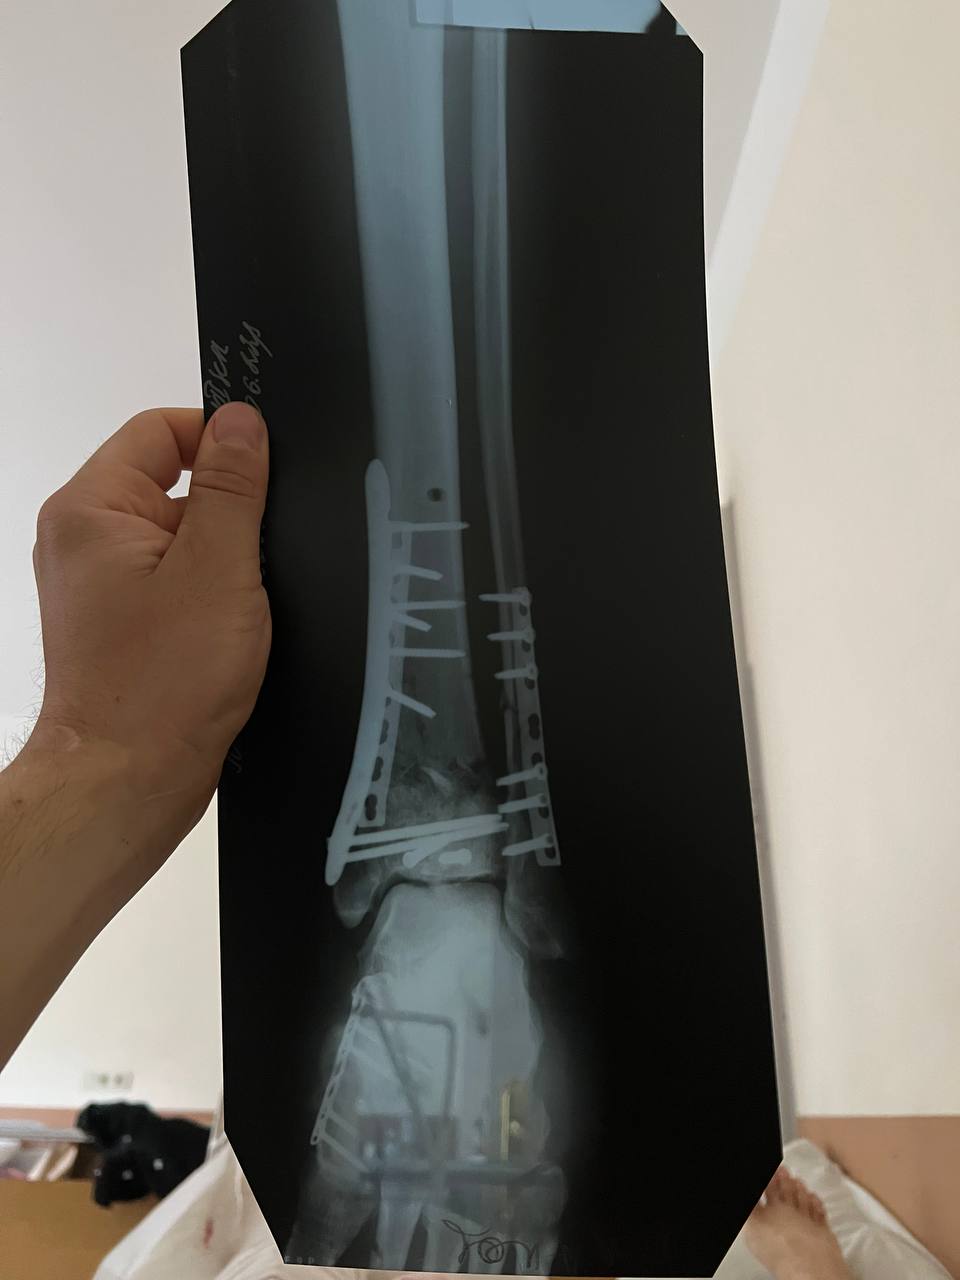

У Руслана був закритий перелом лівої ноги - кінцівка була зламана нижче коліна до кінчиків пальців. Йому за більш ніж рік провели чотири операції, і зараз замість суглоба три великих гвинти. Також після травми довелося з обох сторін зашивати щелепу.

"Відновлення триває й зараз, вже більше року. Через півроку після поранення почав ставати на ноги. Три місяці я взагалі майже не ставав - організм був практично на нулі, крутилося в голові, не міг спати. Плюс - цілий рік у мене були дуже сильні болі, бо зросталися кістки. Було дуже важко психологічно і фізично. Особливо перші три місяці були дуже важкі. Зрештою почав ходити на двох милицях, потім з однією милицею. Намагався ходити без милиці, але не виходило. І зараз можу пройти лише невелику відстань сам", - ділиться чоловік.